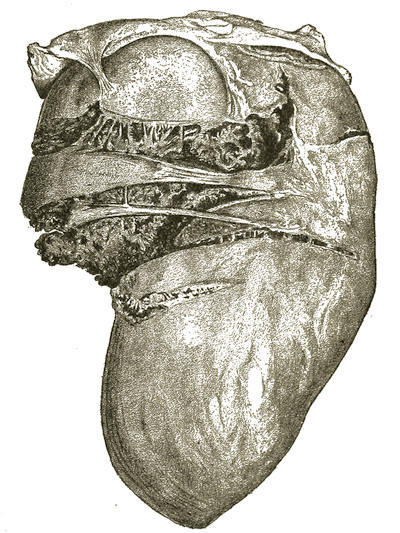

| Medico-Legal Consideration of Death by Mechanical Suffocation. D. S. Lamb, | 705 |